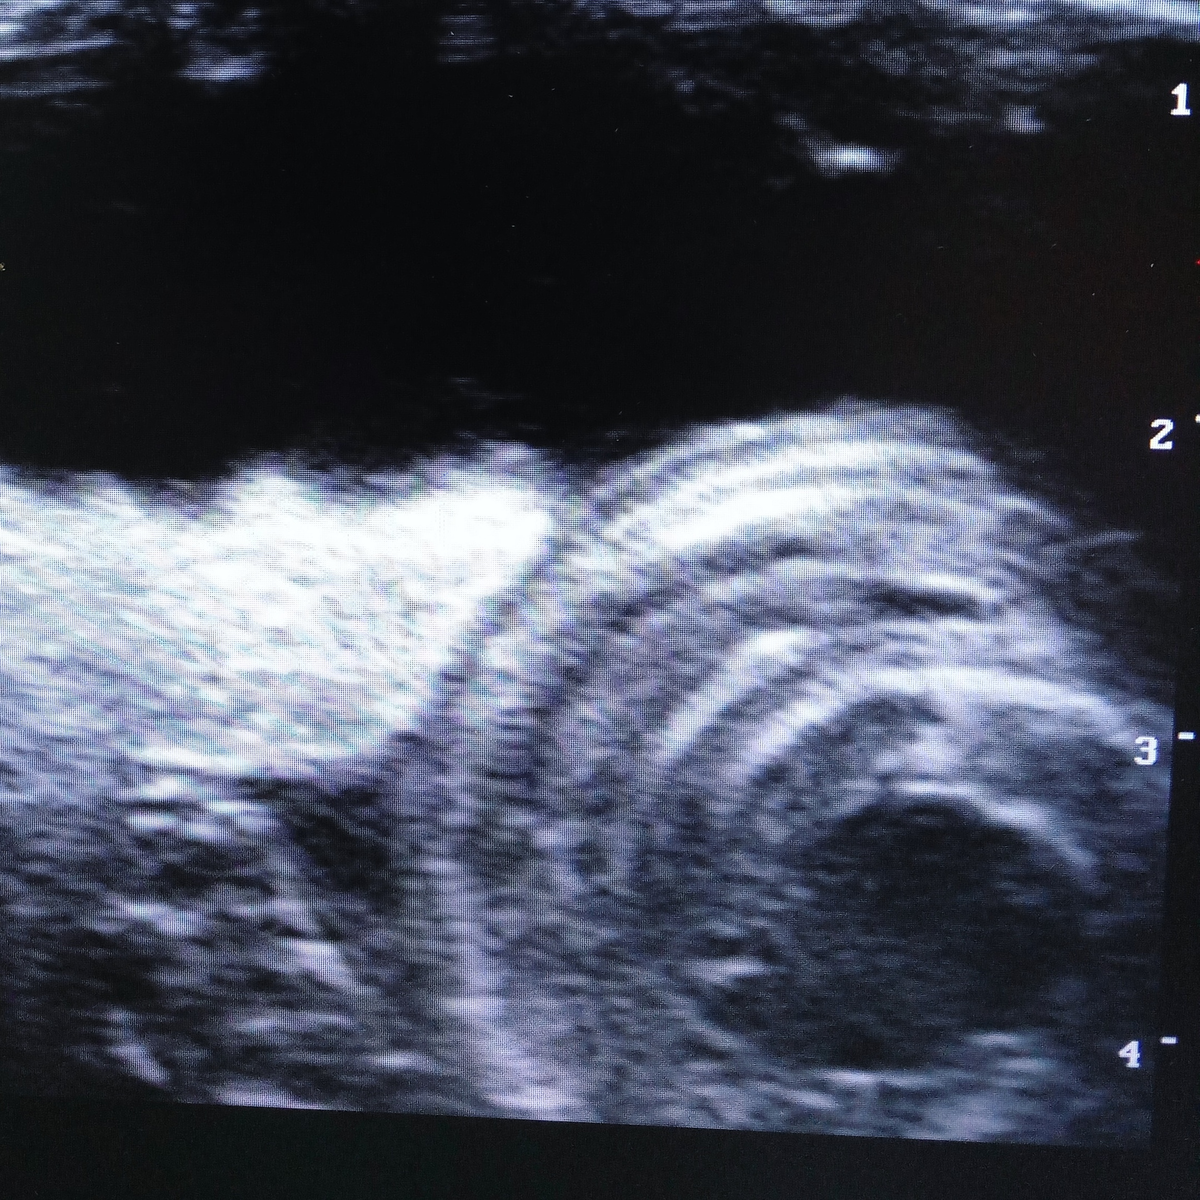

Не каждому ветеринарному врачу удаётся увидеть такие кадры, но нашей коллеге  крупно повезло, на приёме оказалась беременная самка удава обыкновенного.

Срок предполагаемой беременности составлял 4 месяца и на УЗИ картинка была неоднозначная, всё ещё была вероятность, что яйца могут быть неоплодотворённые.

Но уже на контрольном исследовании, которое прошло на днях, чётко видно около десятка молодых удавов, которые совсем скоро порадуют своих владельцев и изрядно поднапрягут соседей.